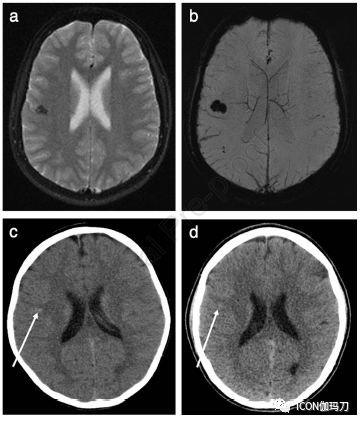

图1、所选神经影像来自15岁男性,急性头痛发作,意识模糊,双下肢无力,左侧较右侧著。在初始头部CT报告为正常的情况下,对持续的无法解释的症状进行MRI检查。(a)复查轴位DWI (b0)显示右侧额叶低信号灶。(b)轴位SWI显示低信号爆米花状病灶,在与(a)相同的位置有明显的开花现象,病灶看起来更大更明显,符合CCM。当在DWI上检测到易感性或开花伪影时,应立即获得正式的SWI,这是我们中心的常规儿科脑部序列。回顾病人先前的影像显示他在6岁时因在学校头部被撞后有过呕吐而进了头部CT检查。(c)头颅轴位CT显示右侧额叶有一个高密度的焦点(箭头),这是急性脑内出血的表现,但没有感觉。(d)审查最近的头部CT显示在同一位置确定有一个微妙的高密度局灶(箭头):病灶(c)和(d)位于相同的位置,磁共振证明为CCM。这个患者表明CCM的CT表现微妙和可能会被忽视。在报告儿童头部CT成像时,特别是考虑到脑内出血和明显的局灶神经功能缺陷的可能性,应始终存在有CCM的可能性。如(a)和(b)所示,MRI有助于诊断。